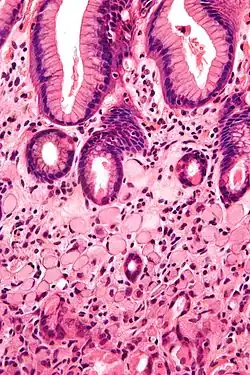

A signet ring cell carcinoma of the stomach. Signet ring cells are seen in the lower half of the image. Gastric epithelium is seen in the upper half of the image. H&E stain.

SRCCs are named due to their resemblance to signet rings, which result from the formation of large vacuoles full of mucin that displaces the nucleus to the cell's periphery.[16]